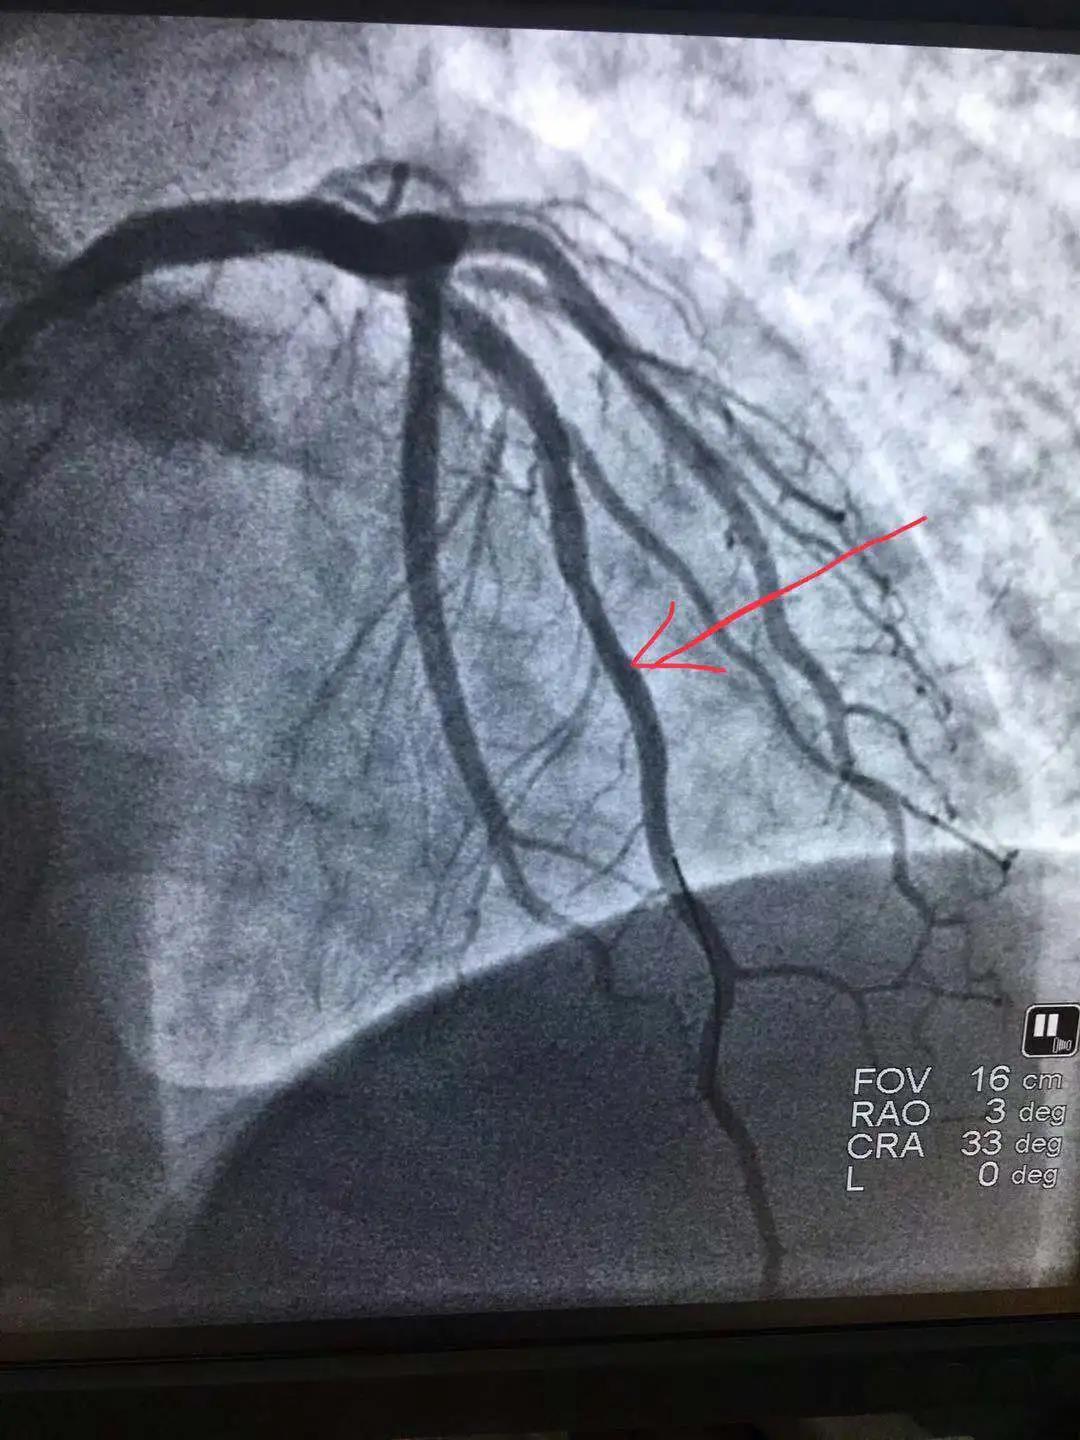

心內(nèi)科醫(yī)務人員冠狀動脈造影中

“冠狀動脈造影”即“冠脈造影”,是診斷冠心病的一種常用方法,作為一種有創(chuàng)診斷技術,它被稱為診斷冠心病的“金標準”。心內(nèi)科融無創(chuàng)與有創(chuàng)協(xié)同治療為一體,硬件設施齊全,配有美國GE大C型臂數(shù)字減影X線造影機,心臟臨時起搏器、床旁監(jiān)護儀、除顫儀、自動分析心電圖等,設有心臟重癥監(jiān)護室(CCU),擁有1個獨立導管室,設有心內(nèi)科??崎T診、心內(nèi)科病房(現(xiàn)有床位71張)、心血管無創(chuàng)檢查室、心電圖室等部門。科室現(xiàn)已熟練開展冠狀動脈造影技術,為心血管疾病患者帶來了福音。